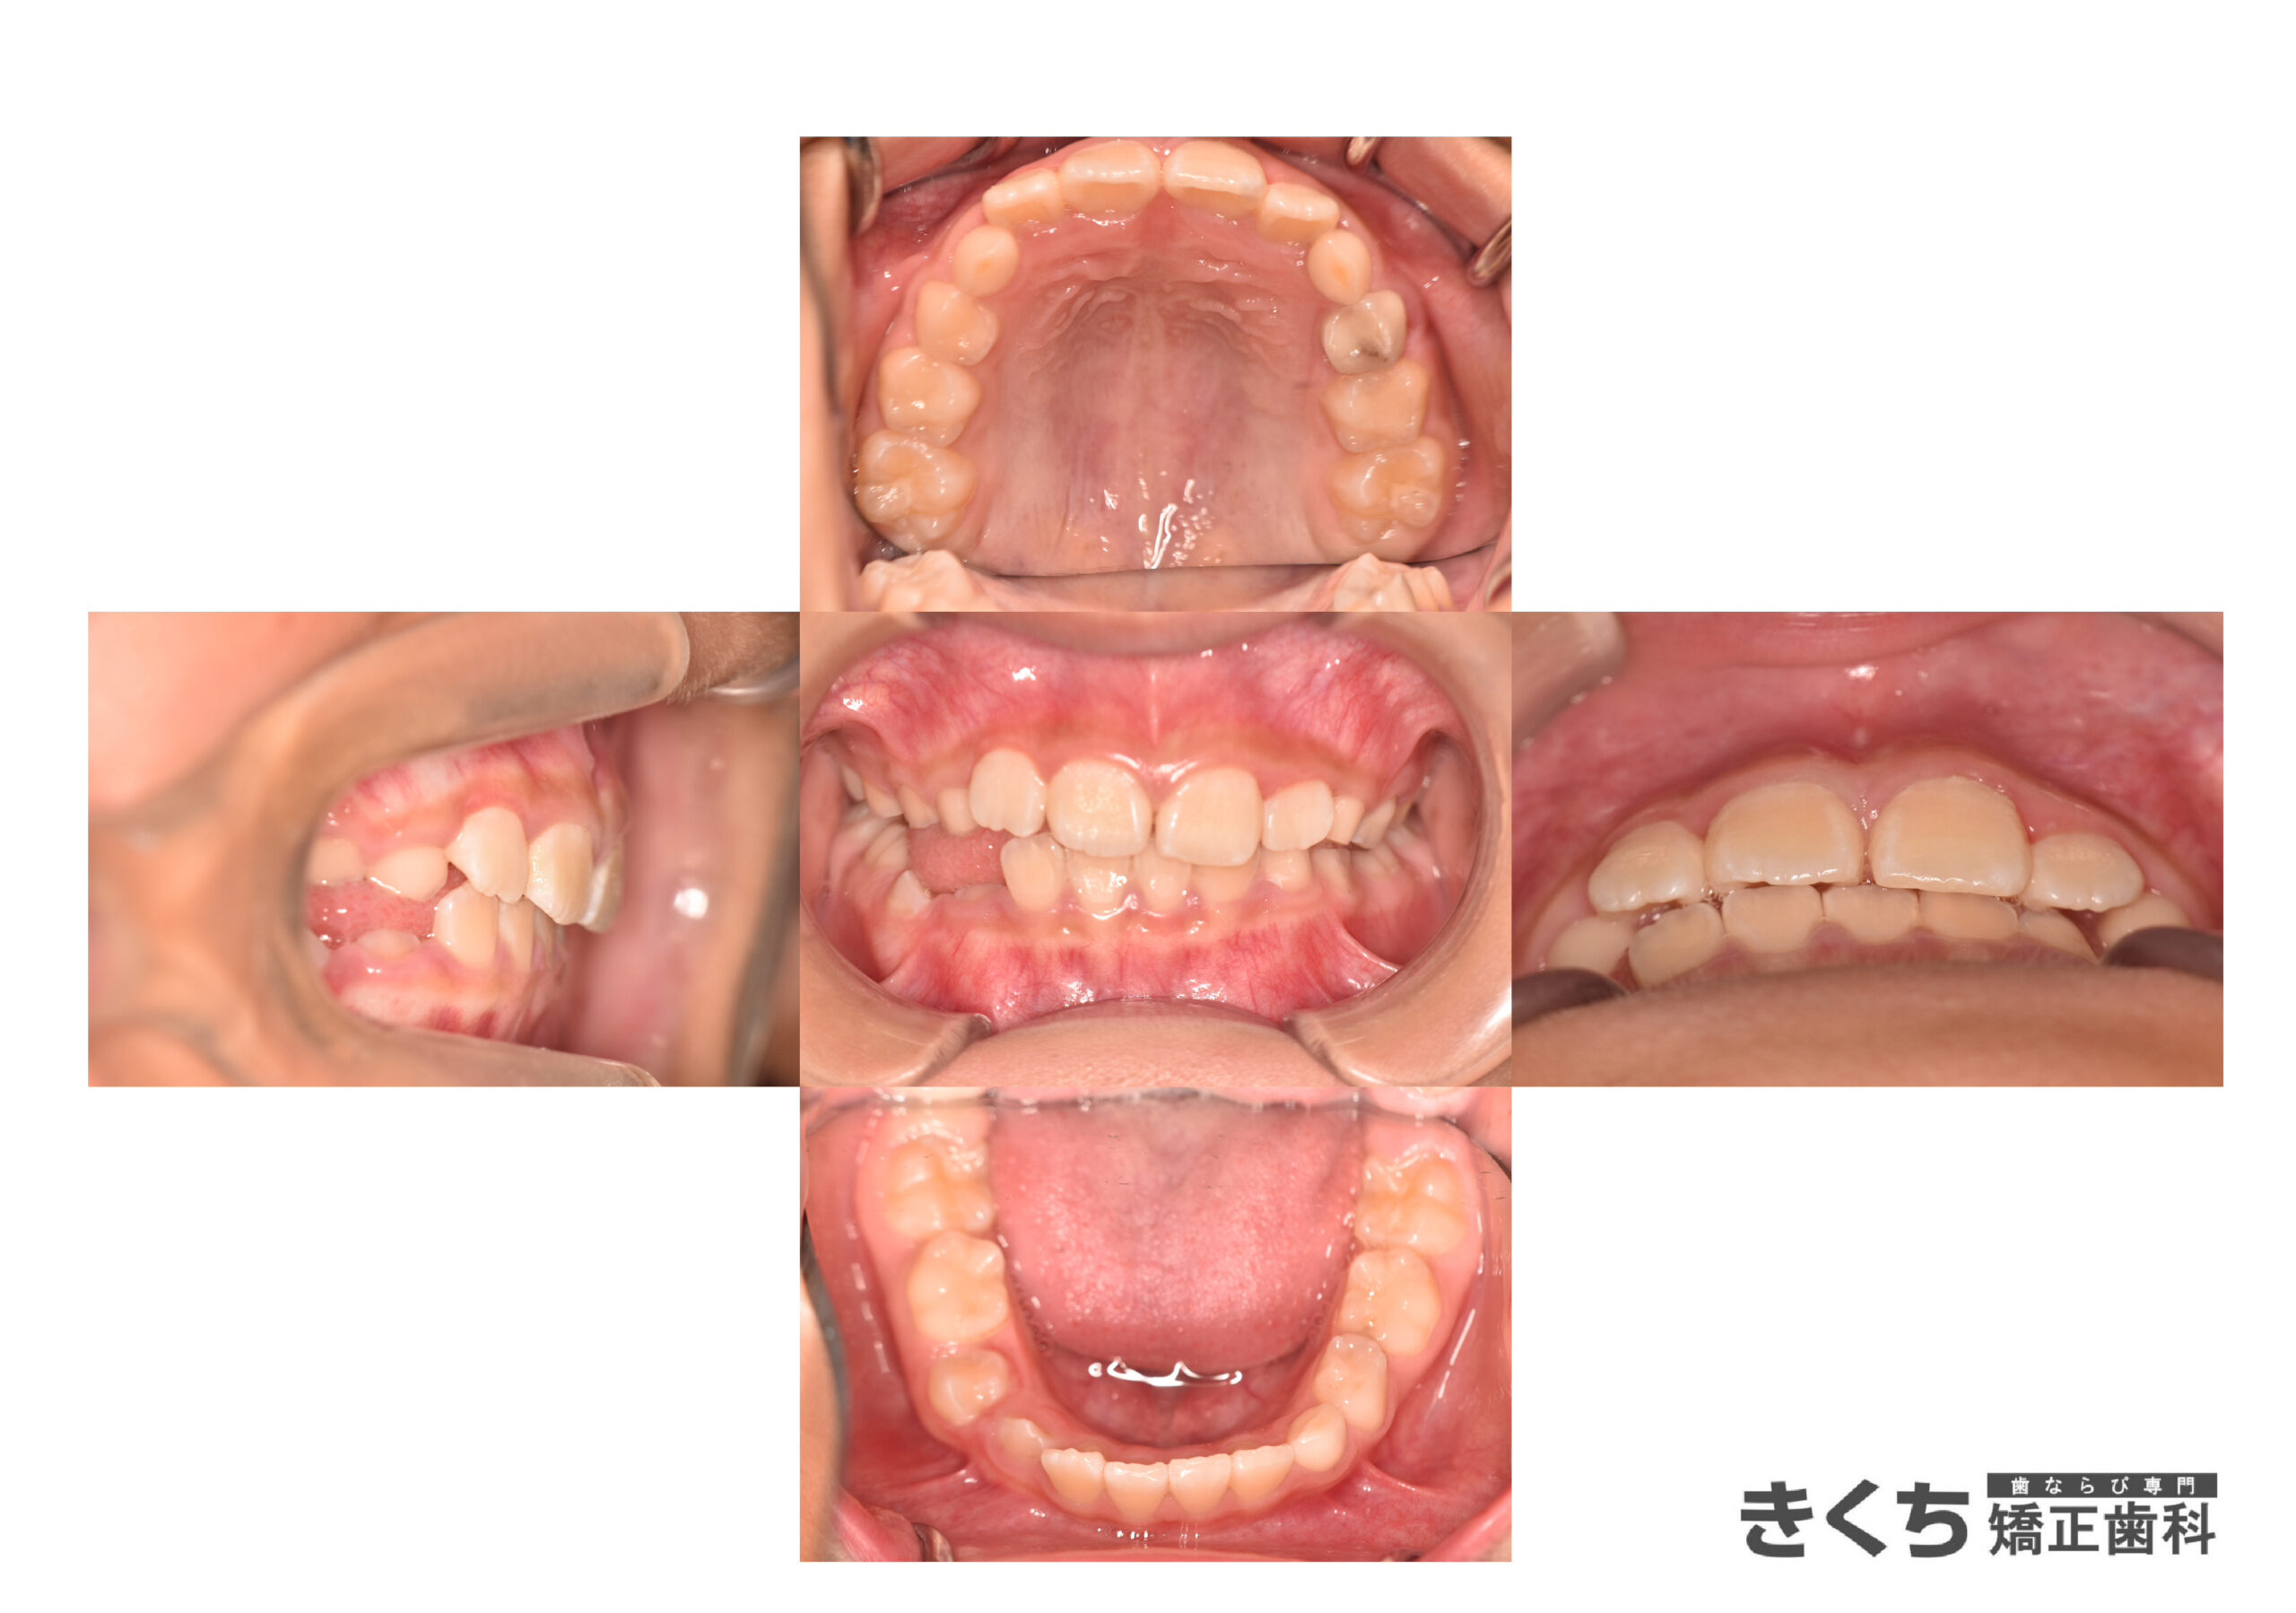

初診時9歳、かみ合わせを気にして来院

口呼吸、舌で上の前歯を押し出す癖がある

他院にて今すぐ矯正治療を始めたほうがいいと指摘を受けた

→6ヶ月ごとのペースで経過観察

口腔筋機能を改善するために指導を行いました。

↓↓↓↓↓↓↓ 6ヶ月後

口腔筋機能 の改善だけで、気にしていたかみ合わせが自然に改善しました。